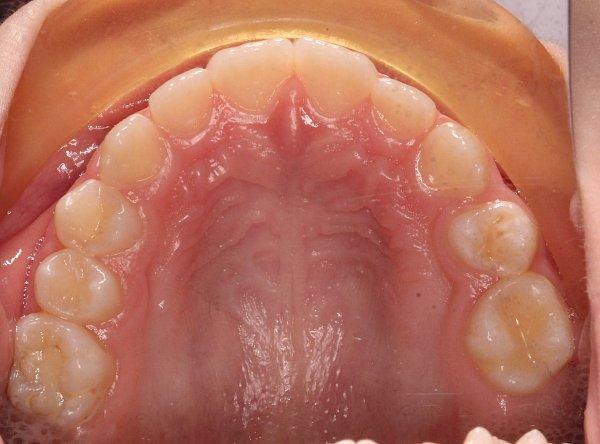

Пациентка 8 лет. Обратились с жалобой на неровное прорезывание зубов и дефицит места для постоянных зубов.

1)использование несъемного аппарата для расширения верхней челюсти Марко Росса

2)Через 4 месяца установка частичной брекет-системы 2 на 4 для выравнивания передней группы зубов;

Срок лечения составил 10 месяцев.

— изменение ширины верхнего зубного ряда, что способствует нормальному прорезыванию постоянных зубов;

— устранена эстетическая недостаточность, связанная со скученностью зубов верхней челюсти.